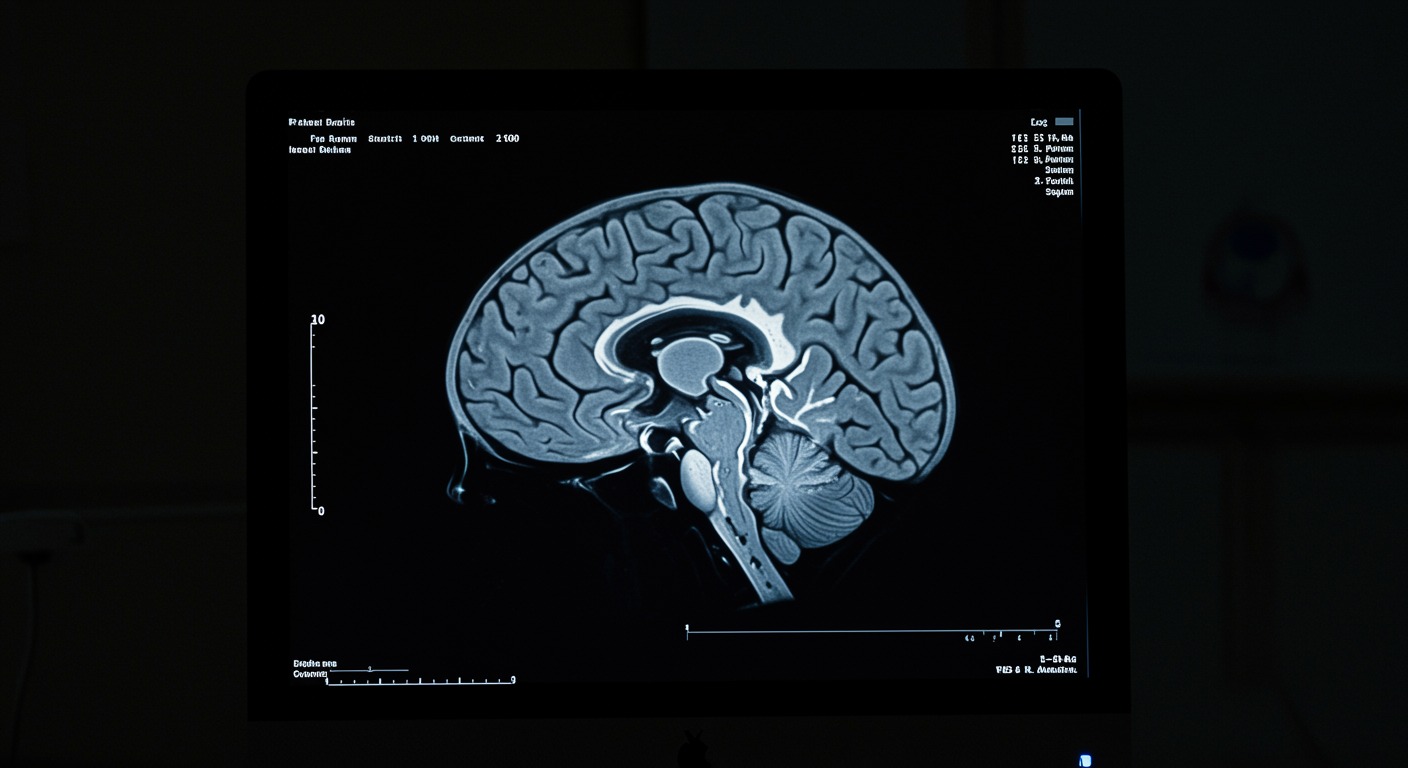

The research shows that chronic HPA axis activation interacts with inflammatory pathways and generates oxidative stress, specifically targeting the hippocampus - a brain region crucial for memory, learning, and mood regulation. This neuroinflammation damages hippocampal neurons and disrupts neuroplasticity, the brain’s ability to adapt and form new connections.

The pathway from chronic stress to depression involves several interconnected mechanisms. Initially, chronic stress triggers persistent HPA axis activation, leading to sustained cortisol release. While acute cortisol elevation is protective, chronic elevation becomes toxic to brain tissue, particularly in the hippocampus which has high concentrations of cortisol receptors.

Elevated cortisol activates inflammatory pathways in the brain, triggering the release of pro-inflammatory cytokines that damage hippocampal neurons. This neuroinflammation also generates oxidative stress, creating reactive oxygen species that further damage brain cells and disrupt normal cellular function.

The damaged hippocampus loses its ability to provide negative feedback to the HPA axis, creating a self-perpetuating cycle where stress responses become increasingly dysregulated. This leads to the characteristic symptoms of depression while also making the brain more vulnerable to future stress-induced damage.